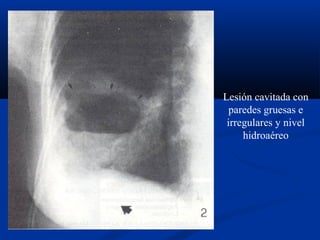

Lesión cavitada con

paredes gruesas e

irregulares y nivel

hidroaéreo

RADIOLOGÍA:

Forma: suelen ser redondeadas, aunque en ocasiones la TBC puede

manifestarse como cavidades irregulares.

- Paredes:

* Finas: bullas y quistes

* Gruesas: Ca. Pulmonar, metástasis, abscesos..

- Contenido:

* Líquido: con o sin nivel hidroaéreo (Q. Hidatídico)

* Masa interior: (signo del menisco): Ca., TBC, abscesos, Q.

Hidatídico (membranas retenidas).

-Situación:

* Campos superiores: TBC

* Campos inferiores: bronquiectasias e infartos

Chest radiographs (posteroanterior and lateral views)